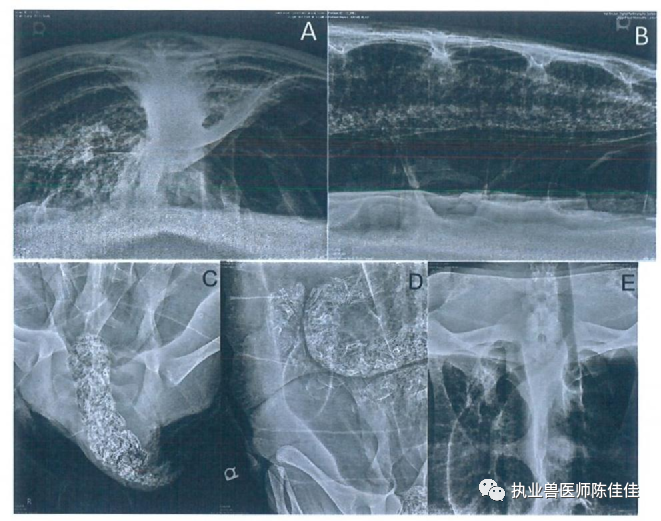

由于经口胃给予矿物油和促动力药物治疗并不能减少胃肠道扩张,因此决定尝试经壳肠穿刺术。海龟的左侧抬高至75°角,因此任何充满气体的肠段都将位于体腔的侧边缘。超声波检查用于识别腹甲中骨结构之间的软组织,从而可以引入20号5.1厘米的针头针头连接到延长线,三通旋塞和60毫升注射器上。将针头通过左侧第三下边缘外侧的结缔组织插入肠腔(图2)。排出约10.3升气体,无并发症随访的X放射图显示,先前压缩的左肺以及位于体腔腹侧底部的肠袢的扩张和轮廓接近正常(图3)。海龟被放回水中,并立即在水面出现中性浮力。那天晚上晚些时候,它能够保持在水下,并被观察到舒适地躺在水箱底部。肠穿刺术三天后,大量粪便含有带血的粘液和约250毫升凝胶状胃肠道脱落组织排出。对该组织的显微镜检查显示坏死的上皮细胞。在此事件发生后,海龟继续排出正常的粪便,随后的超声波检查显示正常的胃肠道循环和摄入。结肠也看起来正常,没有气体膨胀或嵌塞的迹象。尽管浮力障碍已在临床上得到解决,但该动物仍住院了152天,以控制双侧肺炎。在此期间,海龟被维持在前面提到的抗生素治疗方案中,直到临床症状和血液检查允许医疗许可释放。在剩余的住院期间没有发现进一步的并发症;因此,确定该动物已准备好释放,并且不太可能再次出现气体膨胀。

图3:。经肠穿刺术后收集的X光片。(A) 前后视图显示胃肠道气体扩张的消退以及先前压缩的左肺的接近正常的扩张和轮廓。(B) 治疗后的侧视图。(C) 肠穿刺术后的背腹视图和肺炎的解决。